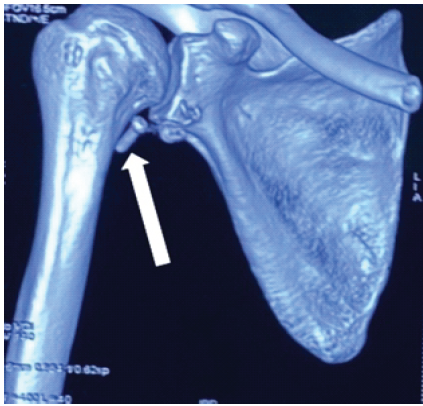

A 38-year-old male with a history of right shoulder instability in the past was managed with the Latarjet procedure 4 years ago. The patient had an uneventful post-surgical period, but symptoms recurred a year later without any significant event. He presented to us with complaints of right shoulder pain and instability since 3 years, having experienced multiple episodes of dislocations, which were managed with closed reduction at different centers. On examination, the Beighton score was five. 1 cm wasting was noted in the right arm. Sensations over the arm were intact. Tests for anterior instability, such as apprehension, relocation-release, and anterior drawer, were positive. There were no signs of instability in posterior and inferior directions. He had a nearly complete range of motion in all planes but was apprehensive to use the arm for overhead activities and lifting heavy objects. X-ray and computed tomography (CT) scan were done, which revealed a displaced as well as a broken screw near the right glenoid, likely from the previous surgery (Fig. 1 and 2). The anteroinferior part of the glenoid appeared to be resorbed. Bone loss was quantified using the perfect circle method in oblique sagittal plane, which was approximately 27% (Fig. 3). Infective etiology was ruled out via clinical examination and radiological investigations.

Figure 2: Computed tomography scan showing resorbed glenoid bone and a displaced screw marked with a white arrow.